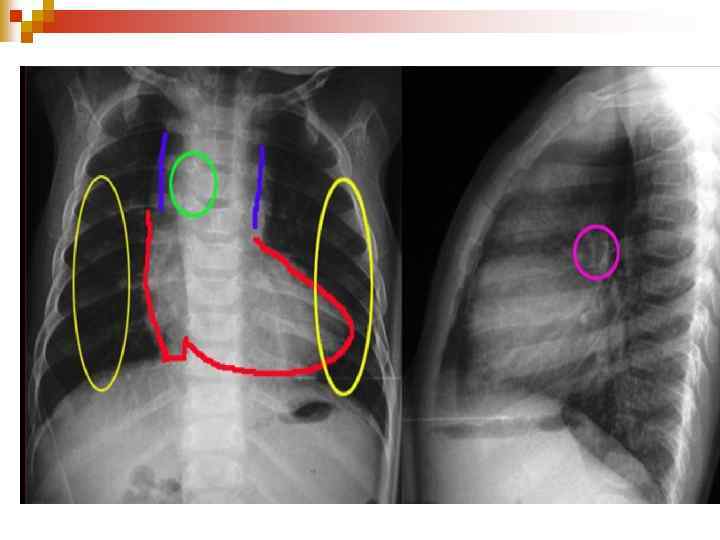

Діагностика ЕКГ: ознаки гіпертрофії ЛШ або обох шлуночків, при склеротичній формі гіпертензії – тільки правого; n Ехо-КГ: візуалізація самого дефекту; n Рентгенологічно: Ш посилення та повнокрів’я легеневого малюнку, розширення коренів легень, збільшення розмірів серця; Ш У період декомпенсації: збіднення легеневого малюнку. n

Диагностика При рентгенологическом исследовании органов грудной клетки описывают форму сердца и состояние легочного рисунка, определяют размер кардиоторакального индекса (КТИ). Все эти показатели имеют свои особенности при разных степенях лёгочной гипертензии. В первой, гиперволемической стадии, выявляется сглаженность талии и погруженность верхушки сердца в диафрагму, увеличение КТИ. Со стороны легочного рисунка отмечается его усиление, нечеткость, размытость. Крайней степенью гиперволемии в лёгких является отёк лёгких. В переходной стадии лёгочной гипертензии отмечается нормализация лёгочного рисунка, некоторая стабилизация размеров КТИ. Для склеротической стадии лёгочной гипертензии характерно значительное увеличение размеров сердца, причем в основном за счёт правых отделов, увеличение правого предсердия (формирование прямого атрио-вазального угла), выбухание дуги лёгочной артерии (индекс Мура более 50%), приподнятость верхушки сердца, которая образует с диафрагмой острый угол. Со стороны лёгочного рисунка часто описывается симптом «обрубленного дерева» : яркие, чёткие, увеличенные корни, на фоне которых лёгочный рисунок прослеживается только до определённого уровня. На периферии имеет место признаки эмфиземы. Грудная клетка имеет вздутую форму, ход ребер горизонтальный, диафрагма уплощена, стоит низко.

Клініка ЗЦ нападу ЕКГ: гіпертрофія ПШ та гіпоксія міокарду; n ЕХО-КГ – визначає величину зміщення аорти, ДМШП, ступінь легеневого стенозу, гіпертрофії ПШ; n Рентгенологічно – серцева тінь має форму дерев’яного чобітка. n